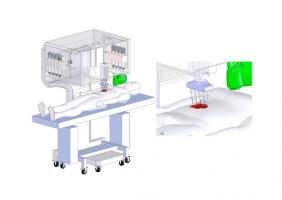

Actualité publiée le 07/06/2021La BIO-IMPRESSION pour réparer la peau et les os pendant la chirurgie

BRULÛRES, GRANDES PLAIES : Une bio-imprimante de peau au chevet du patient